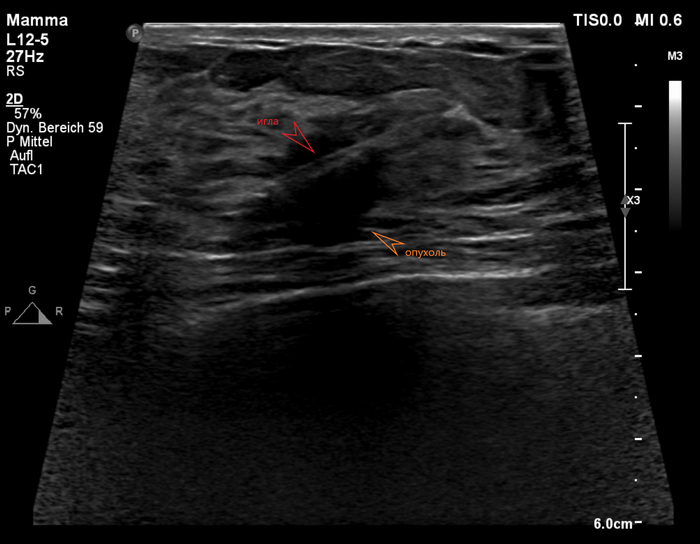

Анамнез: женщина 53-х лет, не имеющая в анамнезе личных или семейных заболеваний, при пальпации было обнаружено плотное и болезненное образование в медиальной части правой молочной железы, которое она впервые заметила примерно месяц назад. Образование постепенно увеличивалось в размерах и оставалось болезненным. Оно располагалось в нижне-внутреннем квадранте железы, в 10 см от соска, и при пальпации представляло собой поверхностное подкожное образование. Не было никаких изменений кожи, выделений из соска или системных симптомов. Результат УЗИ: При прицельном ультразвуковом исследовании было обнаружено овальное, ограниченное, параллелепипедное гипоэхогенное образование с небольшими кистозными участками и задним акустическим усилением. Образование размером 0,8 × 0,8 × 0,4 см располагалось в подкожной клетчатке, непосредственно под дермой, без видимой связи с кожей. Не было обнаружено внутренней васкуляризации, прилегающих воспалительных изменений, а также измененных внутригрудных или подмышечных лимфатических узлов. Результаты ММГ см. выше. Несмотря на доброкачественный вид, новообразование было классифицировано как BI-RADS 4 из-за появившейся боли, недавнего роста и отсутствия предыдущих исследований для сравнения. Была проведена тонкоигольная биопсия под контролем УЗИ, которая выявила пролиферацию веретенообразных клеток в пучках с участками Антони А и В. Иммуногистохимия показала диффузную экспрессию S-100 и Sox10, что подтвердило наличие доброкачественной шванномы.